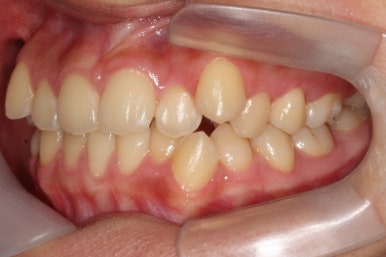

부산교정전문의 키다리아저씨치과에 처음 내원하셨을 때 당시의 입안 모습입니다.

윗니 뿐만 아니라 아랫니 부위에도 덧니가 관찰됩니다. 다른 앞니, 어금니 부위도 약간 삐뚤한 부분이 보입니다.

이 환자분은 발치교정으로 덧니를 개선하기로 하였습니다.

덧니를 뽑는 것이 아니라, 송곳니 뒤쪽의 작은 어금니를 뽑게 됩니다.

송곳니는 크고 튼튼하고 매우 중요한 치아이므로 함부로 뽑으면 안됩니다. 대신 송곳니 뒤쪽의 한 쌍의 작은 어금니 중 하나를 택하여 뽑게 되고, 일반적으로 위아래좌우 총 4개의 치아를 균형있게 뽑게 됩니다.